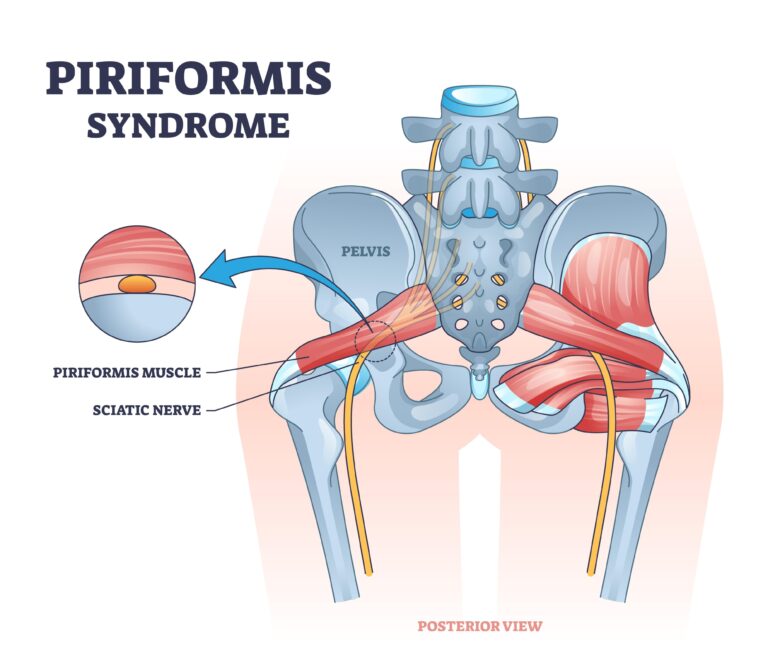

برای درک بهتر “درد جلوی زانو”، ابتدا باید با ساختار این ناحیه آشنا شویم. کانون اصلی این درد، مفصل پاتلوفمورال است؛ یعنی محلی که استخوان کشکک (Patella) در یک شیار در انتهای استخوان ران (Femur) به نام شیار تروکلئار (Trochlear Groove) میلغزد.

در حالت طبیعی، کشکک باید به نرمی و در مرکز این شیار بلغزد. درد جلوی زانو معمولاً زمانی ایجاد میشود که به دلیل عوامل مختلف، این حرکت از مسیر صحیح خود خارج شده و کشکک به یک سمت (اغلب به سمت خارج) منحرف شود. این انحراف باعث افزایش فشار، سایش و تحریک غضروف پشت کشکک و استخوان ران زیرین آن میشود.

- ضعف عضلات لگن و سرینی (Hip and Gluteal Weakness): این مهمترین و شایعترین علت ریشهای است. بهویژه ضعف عضله سرینی میانی (Gluteus Medius) باعث میشود هنگام فعالیتهایی مانند دویدن یا پایین آمدن از پله، لگن به سمت مقابل افتاده و ران به سمت داخل بچرخد. این چرخش داخلی، مسیر حرکت کشکک را به سمت خارج منحرف کرده و باعث سایش و درد میشود.

- ضعف و عدم تعادل در عضله چهارسر ران: بهویژه ضعف بخش داخلی این عضله (Vastus Medialis Obliquus – VMO) نسبت به بخش خارجی آن (Vastus Lateralis)، میتواند تعادل نیروهای وارده بر کشکک را بر هم زده و آن را به سمت خارج بکشد.

- مشکلات ساختاری و بیومکانیک پا: صافی کف پا یا پرونیشن بیش از حد مچ پا باعث چرخش داخلی استخوان درشتنی شده و مسیر حرکت کشکک را مختل میکند.